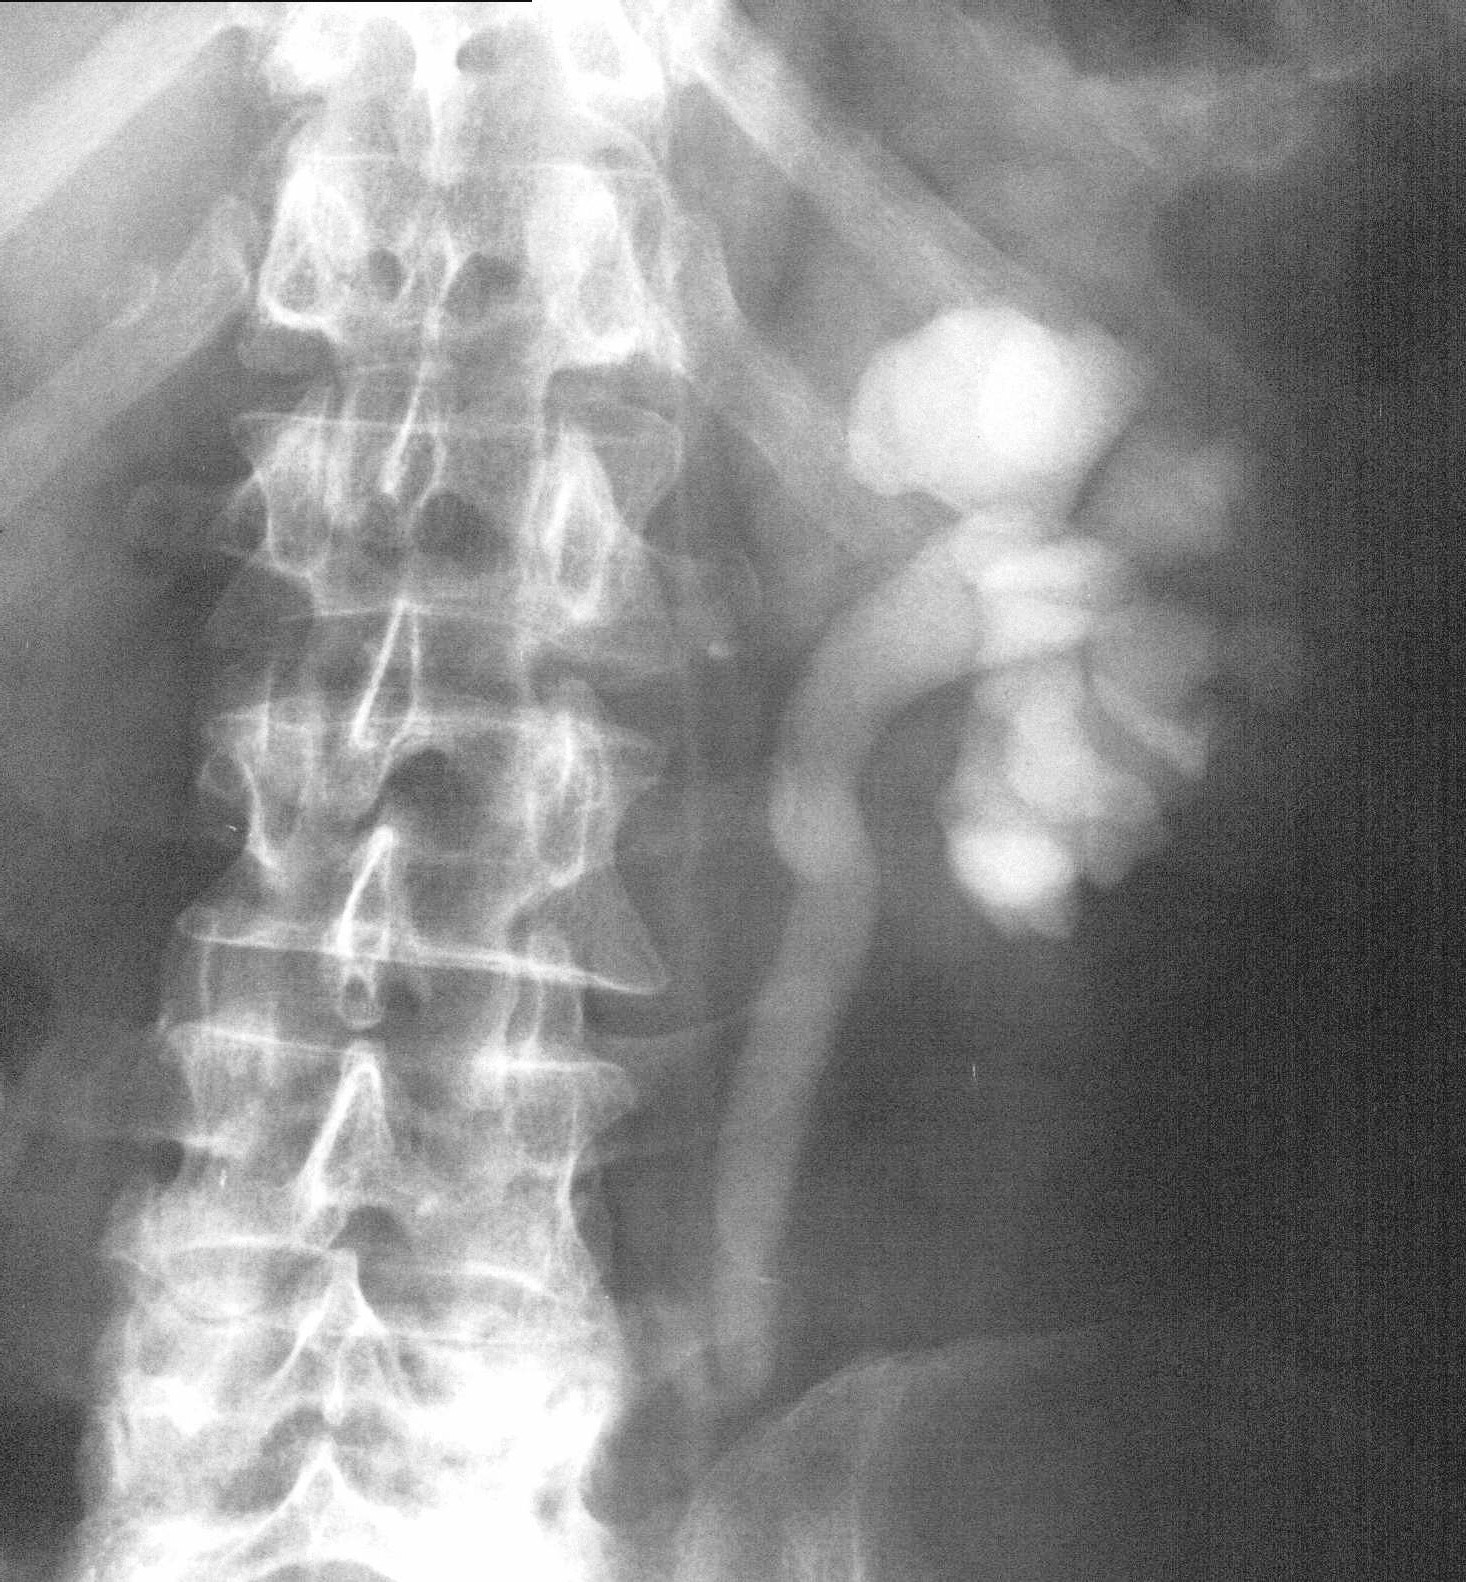

- Figure 5: Retrograde pyelogram showing multiple cavities in the right kidney caused by TB caseous necrosis